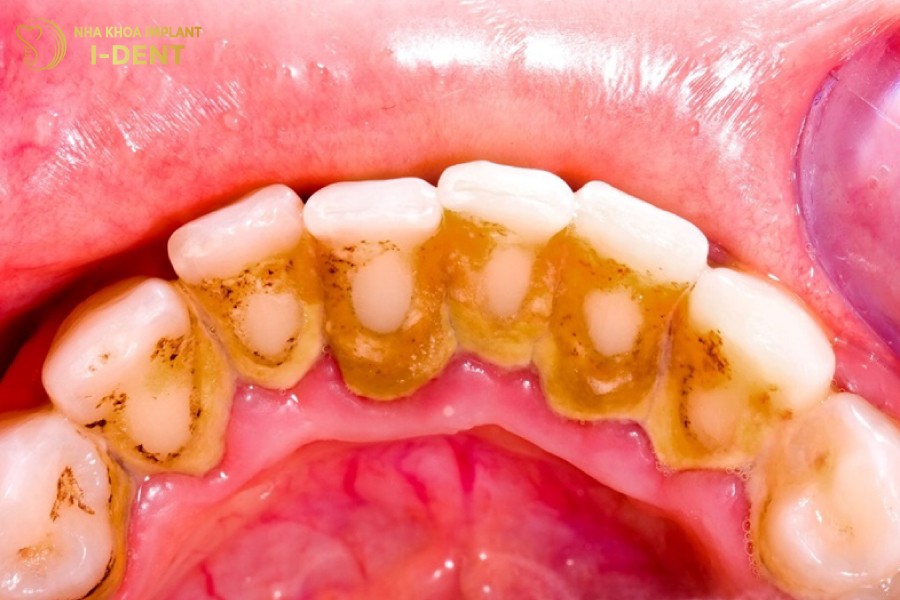

Cao răng/vôi răng là gì? Trong quá trình ăn uống hàng ngày luôn có những mảnh vụn thức ăn còn sót lại trong miệng, mặc dù đã vệ sinh răng vẫn khó có thể làm sạch hết được. Lâu ngày, những vụn thức ăn dư thừa này sẽ bị vôi hóa bởi vi khuẩn, muối Canxi carbonat, Calcium phosphate có trong nước bọt và bắt đầu hình thành cao răng.

Lớp vôi răng bám chặt ở chân răng, không thể làm sạch bằng các dụng cụ vệ sinh thông thường

Cao răng lắng đọng thành lớp dày ở thân răng, nướu răng, có màu trắng đục hoặc vàng nâu gây mất thẩm mỹ và tổn hại đến sức khỏe răng miệng như là: